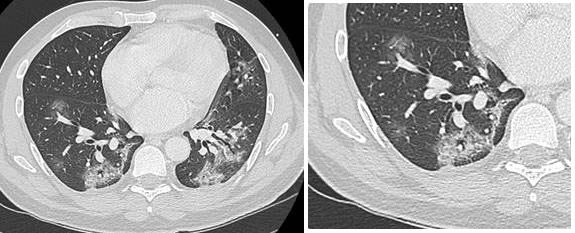

- Des condensations parenchymateuses de forme linéaire (Fig. 2b et 3)

A Gustave Roussy, une des difficultés est l’association fréquente à des lésions pulmonaires secondaires ou des anomalies parenchymateuses liées aux traitements rendant le diagnostic potentiellement difficile. La comparaison radiologique est donc particulièrement utile pour aider au diagnostic (Fig. 3).

Figure 3 : apparition de plages de verre dépoli bilatérales avec un aspect de pneumopathie (condensation) à droite, sur le scanner de mars, alors que le patient était suivi pour des lésions secondaires pulmonaires visibles en janvier 2020 ; patient de 76 ans, altération de l’état général. Le suivi évolutif est utile pour différencier ces nouvelles lésions très évocatrices d’infection Covid-19. Le diagnostic de Covid-19 a été confirmé après le scanner.